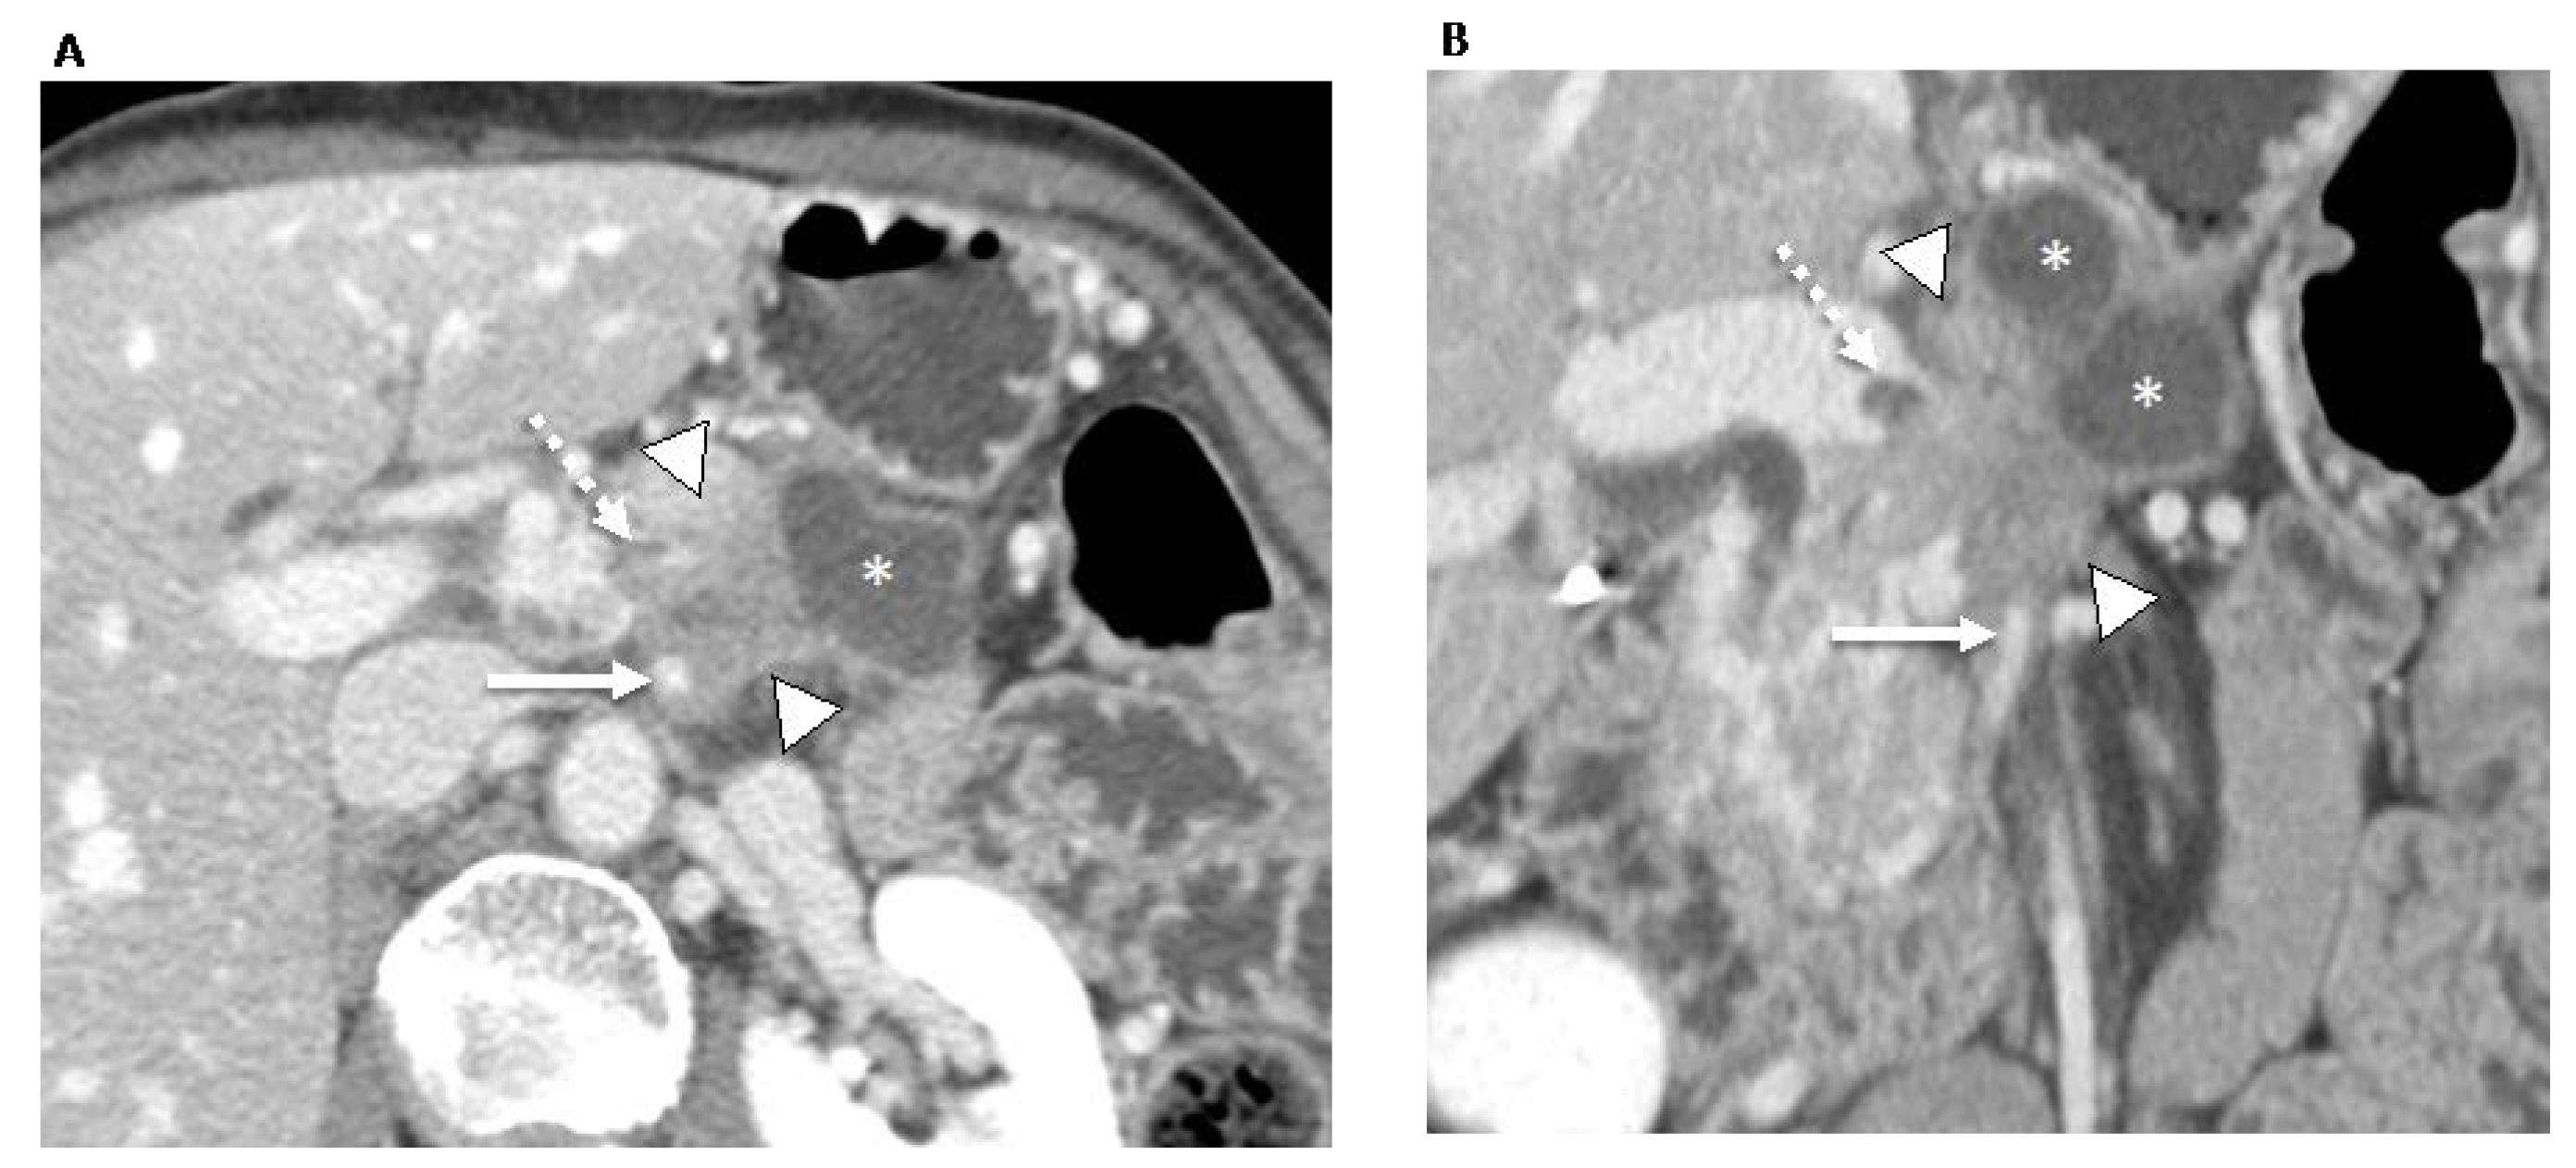

- Marchegiani, G.; Todaro, V.; Boninsegna, E.; Negrelli, R.; Sureka, B.; Bonamini, D.; Salvia, R.; Manfredi, R.; Pozzi Mucelli, R.; Bassi, C. Surgery after FOLFIRINOX treatment for locally advanced and borderline resectable pancreatic cancer: Increase in tumour attenuation on CT correlates with R0 resection. Eur. Radiol. 2018, 28, 4265–4273. [Google Scholar] [CrossRef]

| Marchegiani et al. [36], 2018 (Italy) | 59 | -Tumor attenuation -Longest tumor dimension -Response according to RECIST criteria -Resectability status according to the Americas Hepato-Pancreato-Biliary Association (AHPBA) guidelines | -Chemo -CRT | 2 radiologists | -Only an increase in mean tumor attenuation in the arterial and venous phases following neoadjuvant therapy was significantly associated with R0 resection (p < 0.001 and 0.001 for the arterial and venous phases, respectively). |